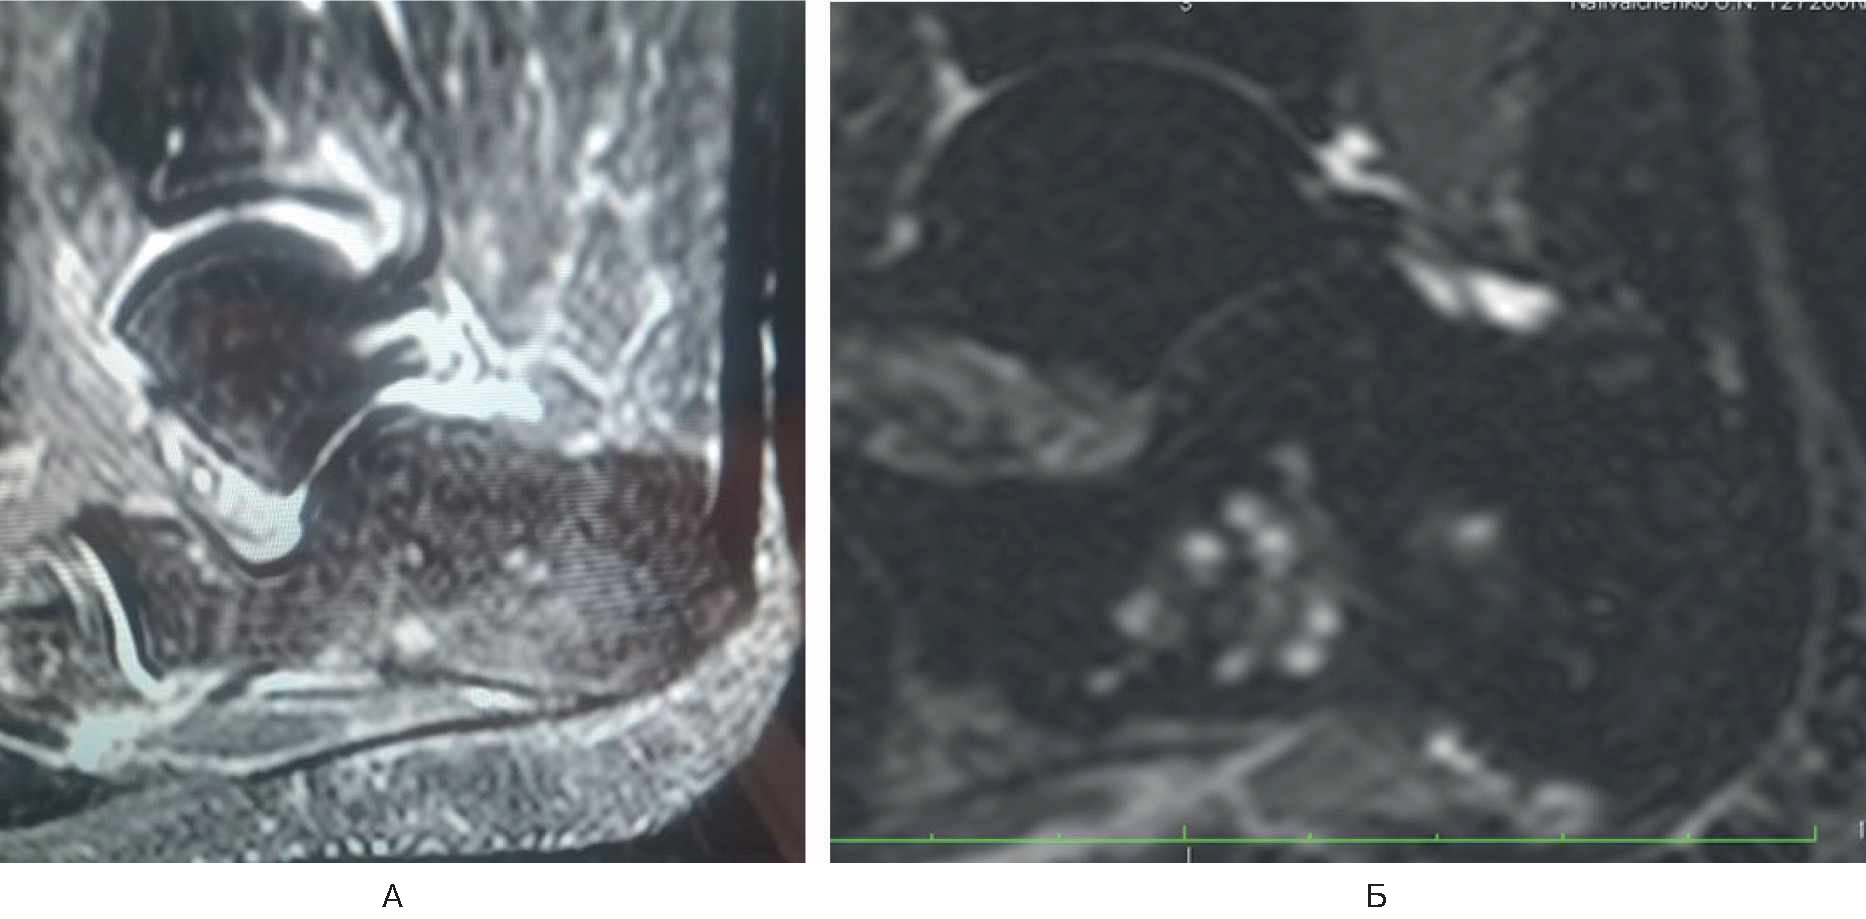

Спустя 6 мес стала отмечать боль (8 баллов по ВАШ) в области нижнего полюса надколенника в покое и при нагрузке, резкую боль – в нижнем полюсе надколенника при активном и пассивном сгибании в коленном суставе. Обратилась в травматолого-ортопедическое отделение. Семейный и соматический анамнез не отягощен. В феврале 2022 г. провели МРТ коленного сустава, обнаружен асептический некроз нижнего полюса надколенника (рис. 2). Выполнена артроскопия коленного сустава с декомпрессией очага некроза.

Рис. 2. МРТ коленного сустава у пациентки Б. Диагноз – асептический некроз нижнего полюса надколенника.

В раннем послеоперационном периоде пациентка отмечала снижение боли (интенсивность – 3 балла по ВАШ). Назначены терипаратид подкожно 20 мкг 1 раз в сутки в течение 2 мес и ношение ортеза на коленный сустав. На контрольный осмотр не явилась.

Лечилась у невролога консервативно с мая по сентябрь 2021 г. без положительной клинической динамики, а с сентября по декабрь 2021 г. – у травматолога по месту жительства по поводу тендопатии. Положительной клинической динамики не было. В марте 2022 г. на приеме у ортопеда выполнена МРТ правой стопы, диагноз – асептический некроз тела пяточной кости (рис. 4А).

Рис. 4. МРТ правой стопы у пациентки Г.

В марте 2022 г. произведена транскутанная остеоперфорация тела правой пяточной кости. Назначен терипаратид 20 мкг подкожно 1 раз в сутки. МРТ-контроль через 1 мес. На контрольном осмотре: пациентка отмечает восстановление функции правой нижней конечности, отсутствие болевого синдрома в правой пяточной кости (0 баллов по ВАШ). По данным контрольной МРТ – положительная динамика, отсутствуют признаки асептического некроза (см. рис. 4Б).

Обсуждение. При изучении публикаций авторами статьи не получены убедительные данные о влиянии COVID-19 на развитие остеонекроза. X.H. Xie и соавт. приводят различные механизмы остеонекроза, включая аномалию

А – асептический некроз тела пяточной кости; Б – отсутствие признаков асептического некроза.